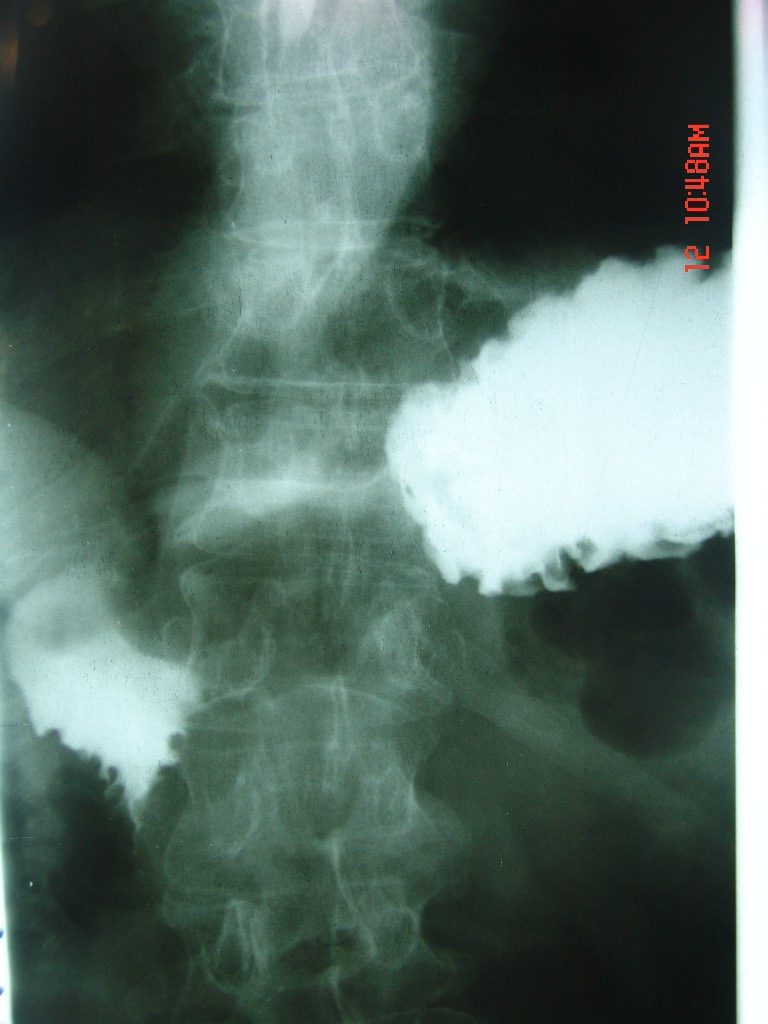

胃体部粘膜不规则增厚,胃肠造影也显示充盈缺损-胃溃疡?胃癌?

十二指肠降段扩张,水平段狭窄成鼠尾状,肠壁明显增厚,胰腺勾突增大成不均匀强化,其内可见低密度区,胆囊增大,1十二指肠水平段腺癌侵犯胰腺勾突可能大,2胰腺癌侵犯十二指肠(只有胆囊增大没有肝内外胆管扩张不好解释)代除外.

上消化道造影见十二指肠结节状充盈缺损,ct增强十二指肠壁局限性增厚并强化,考虑十二指肠壶腹癌?

十二指肠降段扩张,水平段狭窄成鼠尾状,肠壁明显增厚,胰腺勾突增大成不均匀强化,其内可见低密度区,胆囊增大,1十二指肠水平段腺癌侵犯胰腺勾突可能大,2胰腺癌侵犯十二指肠 。

十二指肠降段扩张,水平段狭窄成鼠尾状,肠壁明显增厚,胰腺勾突增大成不均匀强化,,胆囊增大,十二指肠水平段腺癌侵犯胰腺